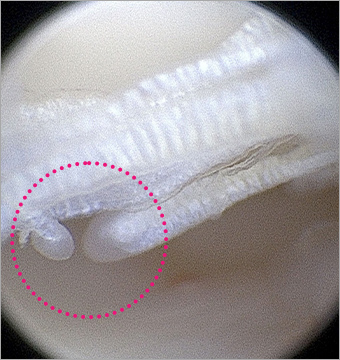

단열된 십자인대

단열된 십자인대

정상 반월판의 물결 모양

(Oyster flounce)

본원 시술 사진